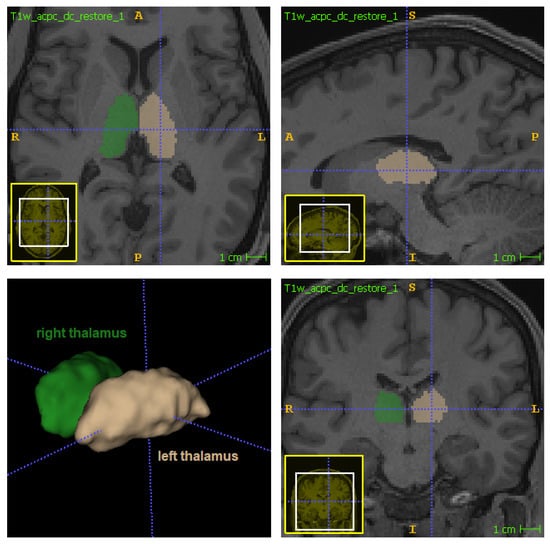

The thalamus (Figure 1) is a bilateral subcortical brain structure. Each of its two parts measure on average 20 mm in the left–right direction (radiological convention) and 30 mm in the anterior–posterior direction [1]. It is located in the central region of the brain, below the ventricles and fornix, and above the hypothalamus (Figure 1 and Figure 2). Despite its relatively small volume, the thalamus can be further divided into nuclei depending on the cytological differences existing across different regions of the same structure [1]. The thalamus also has a central physiological role in the nervous system, functioning as a signal transponder owing to the white matter connecting it to a wide area of the cortex. Furthermore, it is involved in other functions, including the regulation of sleep, alertness, motor functions, and spoken language [1,2].

Figure 1.

The thalamus’s structure and location in the brain.

Figure 2.

Location of thalamus in orthogonal views: left thalamus in beige (label 10 in FreeSurferColorLUT) and right thalamus in green (label 49 in FreeSurferColorLUT).